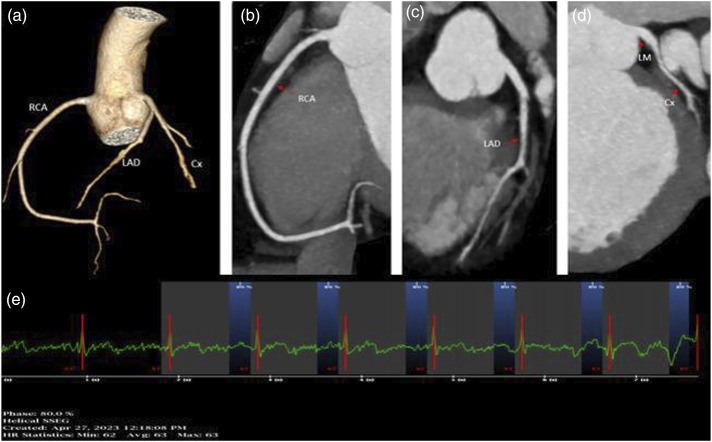

Material and methods: A Retrospective study including 103 patients (64M, 39F) who underwent coronary computed tomography was retrospectively examined at a single center. PCAT and high-risk plaques were measured independently and compared to stenosis and coronary artery type. Adipose tissue attenuation, ranging from -180 to -25 HU, was measured along the plaque's length and in a 0.5-1 mm region around the perilesional coronary arteries.

Results: The PCAT values increases with the degree of stenosis in the LAD, Cx, and RCA (r = 0.9161, p < .001; r = 0.9717, p < .001; r = 0.9315, p < .001, respectively). PCAT values demonstrate a positive pattern when plaque length increases in all coronary arteries (r = -0.6316, p < .001; r = -0.8825, p < .001; r = -0.7529, p < .001; LAD, Cx, RCA). PCAT values differed significantly based on plaque type in all coronary arteries. Calcified plaques showed statistically significant differences compared to both soft and mixed plaques (p < .05). Patients with positive remodeling had PCAT values of -69.43 (±8.76) HU, while cases without positive remodeling had PCAT values of -84.54 (±7.65) HU, indicating a significant difference (p < .05).

Abstract Image